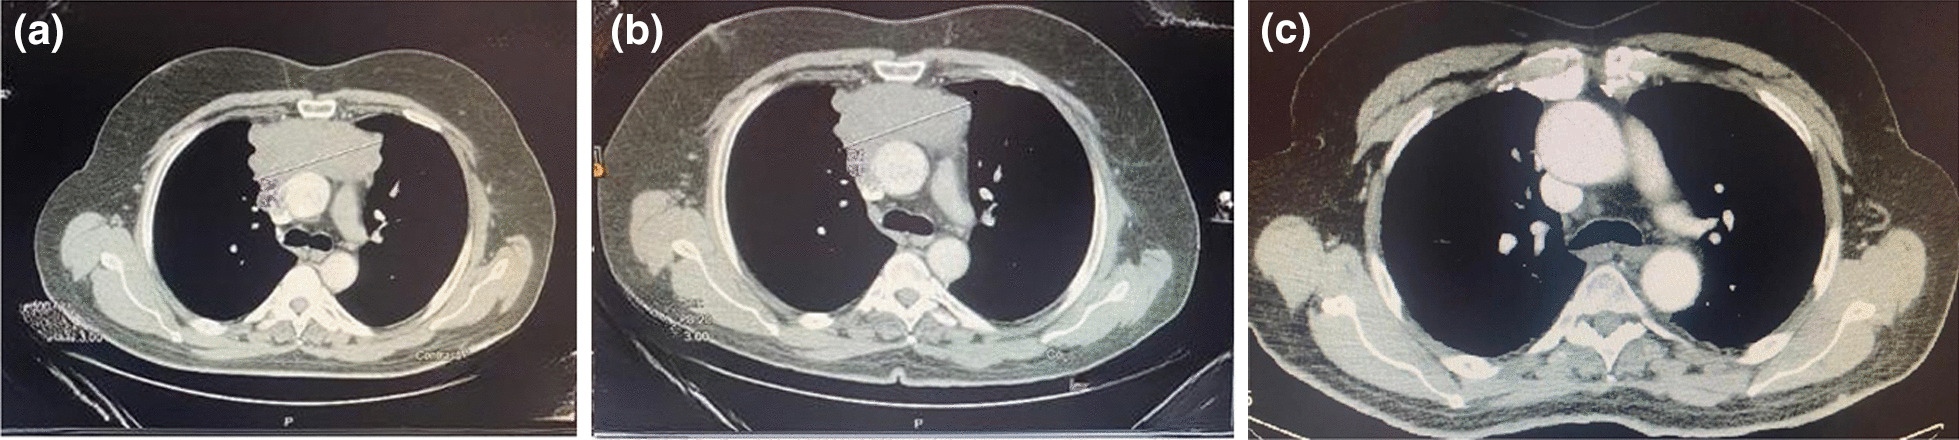

Contrast-enhanced computed tomography (CT) scan was used to delineate clinical staging, tumor size and to detect post-neoadjuvant chemotherapy treatment effect on tumor burden. The response evaluation criteria in solid tumors (RECIST) was used to classify the effect of neoadjuvant chemotherapy (NACT) on tumor burden as complete response (CR), partial response (PR), stable disease (SD) or progressive disease (PD). Comparison was made between pre-neoadjuvant therapy initiation and post-operatively. All images were evaluated by a single expert radiologist (Fig. 1).

Fig. 1.

a Computed tomography (CT) of thymoma tumor pre-neoadjuvant chemotherapy. b Computed tomography (CT) of thymoma tumor post-neoadjuvant chemotherapy. c Chest computed tomography (CT) after surgery